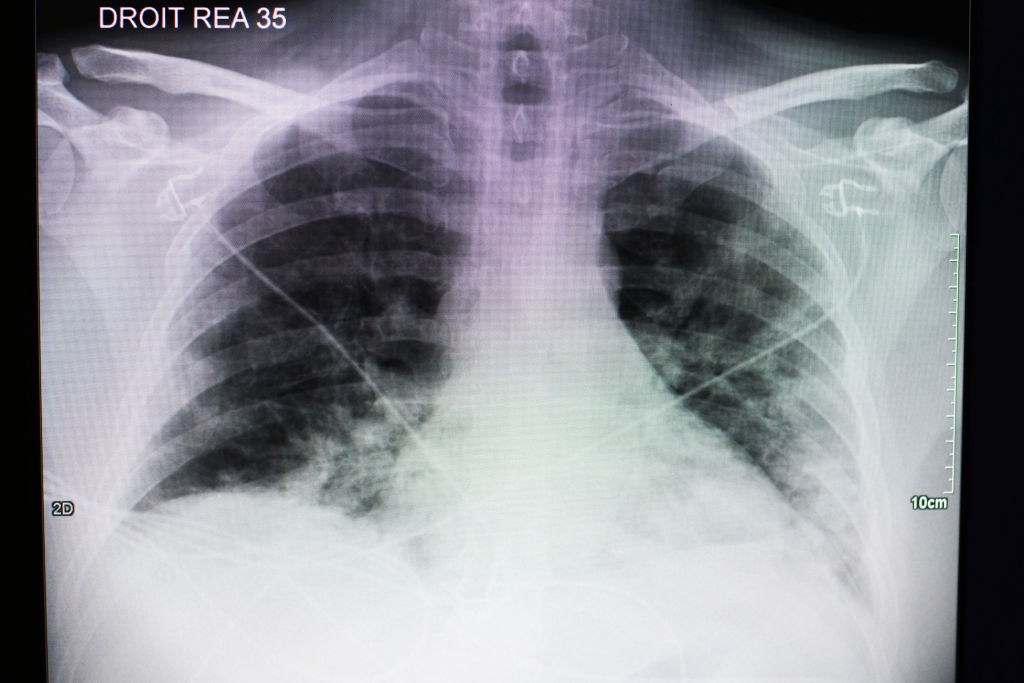

El papá del pequeño se fue a trabajar y horas más tarde su esposa le llamó para decirle que su hijo pedía ayuda porque no podía respirar. El niño fue llevado a urgencias y ahí le hicieron unas placas de tórax donde quedaba evidenciado el gran daño pulmonar que le había provocado el COVID-19, enfermedad que le fue diagnosticada horas después.